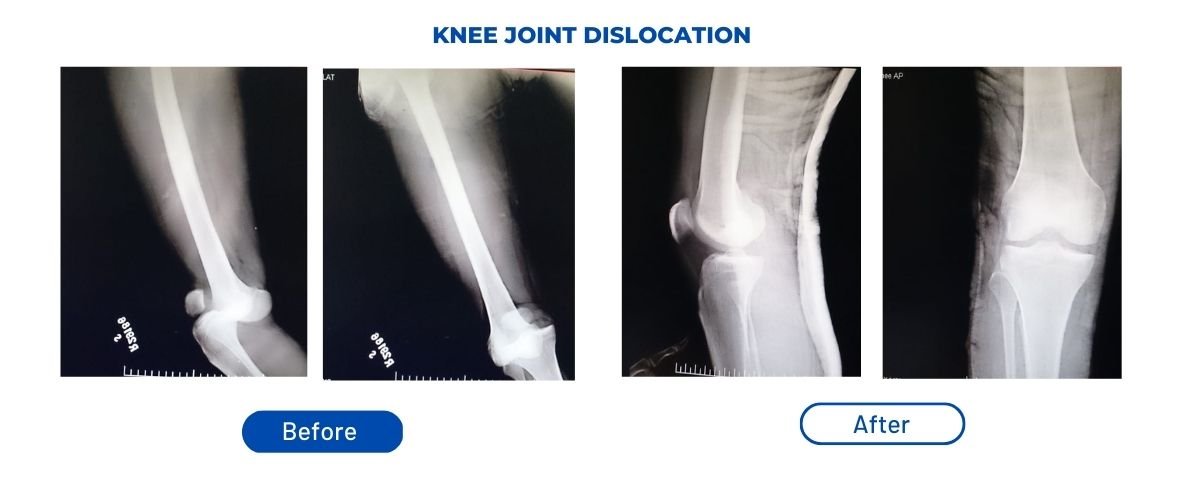

Fracture Treatment Surgery